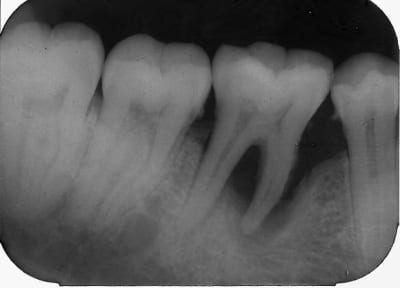

/7 mois après........visite de controle et radio ci joint. Tres agreable

surprise.

*On constate une regeneration de l os alveolaire ds le septum

intraradiculaire et un peu du coté mesiale.*

Visible à fort grossissement.........x 200 %

Disparition totale de la mobilté dentaire........mm solidité que la 37.

Comme le montre la radio, c est une dent saine sans aucune trace de carie. elle l est toujours d ailleurs.